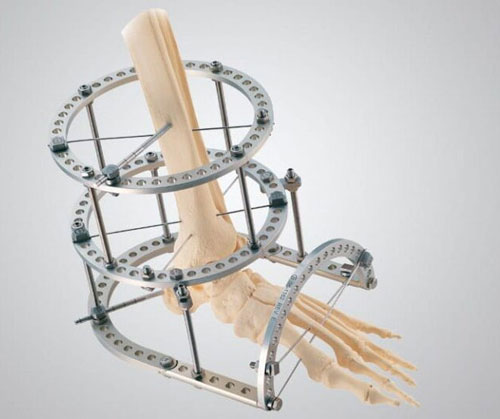

We are dedicated to advancing surgical care through cutting-edge medical technology and trusted partnerships. Specializing in high-performance spinal fusion products, state-of-the-art operating room equipment, advanced orthopedic solutions, and next-generation biologics, we deliver the tools that empower surgeons and improve patient outcomes.